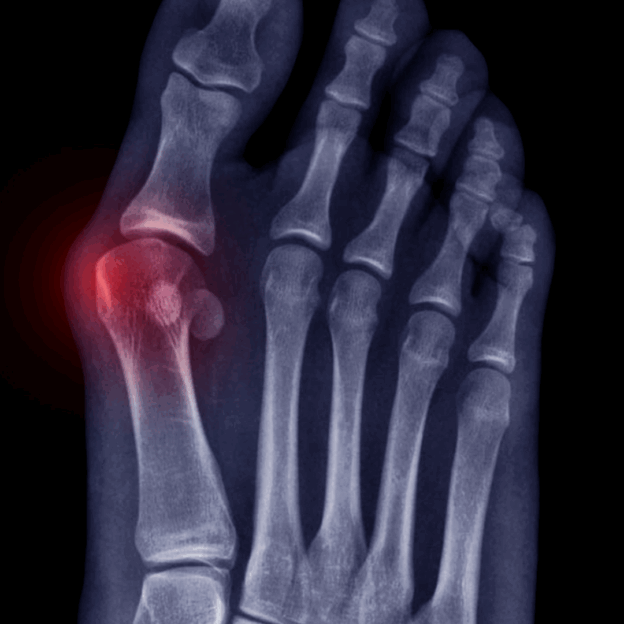

A bunion is a bony bump that occurs at the joint of the big toe. It occurs when proper mechanics aren't practiced, most notably when the ankle is collapsed (pronated), and the foot moves into external rotation (toes positioned away from midline, like a duck). This causes the tip of your big toe to get pulled toward the smaller toes and forces the joint at the base of your big toe to stick out.

Bunions aren't created overnight but are an accumulation of wear and tear. At first, inflammation is sent to the joint when there is excessive stress from standing and walking incorrectly.

This will bring pain to the area, causing a shifting of gait to avoid pressure, and often the addition of ice to deal with the pain and inflammation. Unfortunately, both approaches will lead to a hardening, creating the bunion.